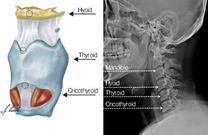

"Upon examining the neck structures, we also saw some fractures of bones which are usually very important in homicides. One of the bones is called the hyoid bone, and there was also the thyroid cartilage bone which had some fractures and hemorrhage,” he said.

Parts of a neck

The hyoid is the U-shaped bone of the neck which breaks during strangulation. The C5 provides sensation to the upper part of your upper arm down to your elbow, while the thyroid cartilage protects the vocal folds which are located directly behind it.